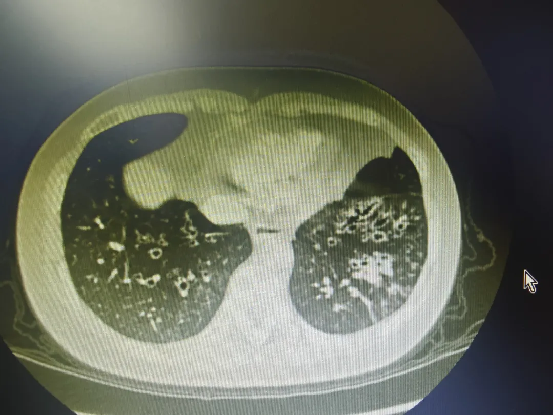

· 影像学金标准——胸部高分辨率CT:这是诊断和评估支扩范围、类型的首要方法。CT上可清晰看到支气管呈囊状、柱状或串珠状扩张,支气管壁增厚,有时可见“轨道征”或“印戒征”。

患者的胸部CT证实了左下肺存在典型的囊柱状支气管扩张。住院后,主管医生根据痰培养结果给予敏感抗生素静脉滴注,同时康复治疗师每日指导他进行体位引流和呼吸训练。因痰液浓稠且量大,初始排痰效果欠佳,经评估后,孙主任为他安排了一次支气管镜下肺泡灌洗治疗。术后,患者当即感觉呼吸顺畅了许多,每日痰量显著减少。